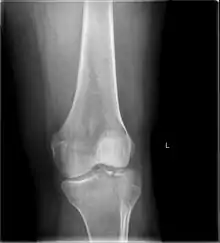

In all injuries to the tibial plateau radiographs (commonly called x-rays) are imperative. Computed tomography scans are not always necessary but are sometimes critical for evaluating degree of fracture and determining a treatment plan that would not be possible with plain radiographs.[5] Magnetic Resonance images are the diagnostic modality of choice when meniscal, ligamentous and soft tissue injuries are suspected.[6][7] CT angiography should be considered if there is alteration of the distal pulses or concern about arterial injury.

Subtle tibial plateau fracture on an AP X ray of the knee

A tibial plateau fracture seen on X-ray